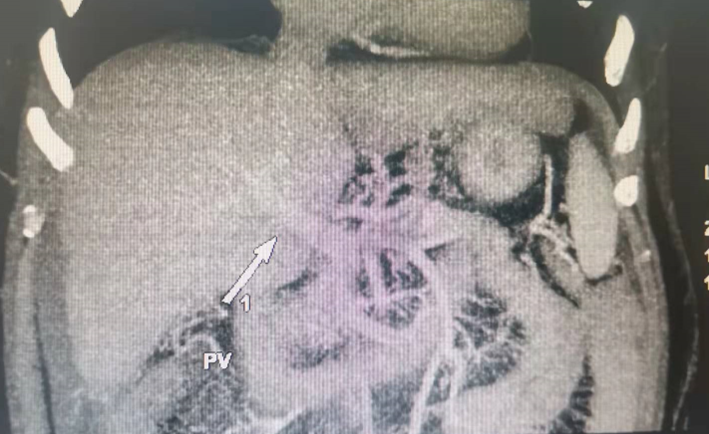

病史资料1、患者男,53岁,间断右胁隐痛2年余,再发黑便伴呕血5小时 2、既往:长期大量饮酒,日均1kg30年,戒断10个月;偶尔吸烟;“高血压”16年,最高达160mmHg,未规律用药;“银屑病”40年;半年前右眼内眦皮肤包块手术,术后病理:基底细胞癌,未特殊治疗 3、查体:肝病面容,贫血貌,腹膨隆,腹壁静脉显露,肝脏剑突下4cm,右肋下3cm可触及,质硬,触痛阳性,移动性浊音阳性,肠鸣音活跃,10次/分。 4、诊断:1、酒精性肝硬化失代偿期(门脉高压、脾亢、腹水);2、上消化道出血;3、高血压病;4、银屑病;5、右内眦基底细胞癌术后辅助检查:ECG:正常心电图;彩超:肝脏体积增大并实质回声弥漫性改变;肝源性胆囊炎,脾大,腹水;门静脉左支内径8mm,右支内径8.5mm。CT平扫加增强:1、肝硬化、脾大、门脉高压; 2、下腔静脉肝段内径稍细,3支肝静脉显影欠清,门静脉左右支均显影。 3、食管胃底静脉见迂曲静脉影2021-10-31检验学指标:血常规:白细胞5.610^9/L,红细胞2.4910^12/L,HB:76g/L,血小板11110^9/L;肝功能;谷丙转氨酶23.9u/L谷草转氨酶15.6u/L,总胆红素39.8umol/L直接胆红素16.5umol/L,间接胆红素23.3umol/L,白蛋白26.3g/L血氨正常;凝血PT:13.7s,INR:1.26,APTT:36.8s,FIB:2.53g/L,D-D:0.5ug/ml;肾功能正常;传染病阴性;肿瘤标志物阴性AFP:3.5ng/ml。Child-pugh分级9分B级MELD(终末期肝病模型)评分R=6分治疗:TIPS及胃冠状动脉栓塞治疗术治疗目的:TIPS:术后短期内总胆红素升高的危险因素:①术中机械性损伤,肝功能受到损伤,相应的肝脏代谢功能也会受到影响,因此,术后短期内容易出现胆红素显著升高现象;②肝内支架分流道长度较长者,容易出现TIPS术后短期内总胆红素显著升高。可能是肝实质内覆膜支架会阻断部分肝内胆管,导致部分胆汁无法排泄,相应的总胆红素也会随之升高,而肝内支架越长,则越容易出现上述情况;③建立覆膜支架分流道后造影,若门静脉左右分支均显影,提示保留部分进肝血流,则术后肝功能损伤相对较小。若门静脉左右分支均不显影,提示门腔分流量较多,一方面分流使肝功能损伤,另一方面间接胆红素不能被肝脏合成而直接排泄,最终导致总胆红素升高。术后门静脉分支显影支数多是保护因素。河南中医药大学第一附属医院周围血管科竭诚为您的健康保驾护航!地址:郑州市人民路19号,第二住院部13楼周围血管科,电话:0371-66232232.